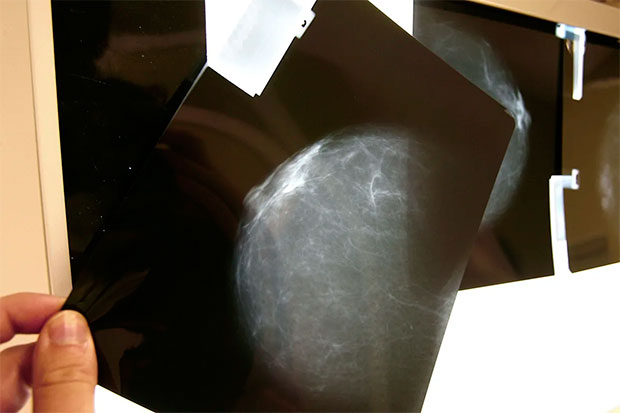

La densidad mamográfica mide la proporción de tejido fibroglandular de una mama, frente a la cantidad de tejido graso. Cuanto más densas, más tejido fibroso tienen y mayor es el riesgo de cáncer de mama.

El 69% de las participantes presentó tumores HR+, un 19% el subtipo HER2+ y un 12% el triple negativo, y la densidad mamográfica media fue del 26%.

Las mujeres con densidad mamográfica superior al 50% presentaron un menor porcentaje de tumores con mejor pronóstico (HR+), mientras que el porcentaje de tumores HER2+ y triple negativo -los más agresivos- fue un 36% y un 23% mayor, respectivamente, en comparación con las mujeres del grupo de menor densidad.

Virginia Lope, líder de la investigación, explica que estos patrones se observaron principalmente en mujeres pre/perimenopáusicas y en aquellas con sobrepeso u obesidad.

“Aunque los hallazgos son preliminares y requieren confirmación, apuntan a que la densidad mamográfica alta podría ser un marcador relevante para identificar a mujeres con mayor riesgo de desarrollar formas más agresivas de cáncer de mama”, concluye.